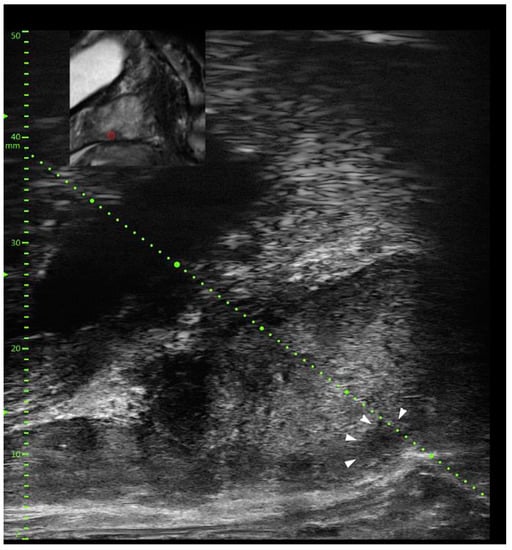

- Cornud, F.; Lefevre, A.; Flam, T.; Dumonceau, O.; Galiano, M.; Soyer, P.; Camparo, P.; Barral, M. MRI-directed high-frequency (29MhZ) TRUS-guided biopsies: Initial results of a single-center study. Eur. Radiol. 2020, 30, 4838–4846. [Google Scholar] [CrossRef]

- Avolio, P.P.; Lughezzani, G.; Paciotti, M.; Maffei, D.; Uleri, A.; Frego, N.; Hurle, R.; Lazzeri, M.; Saita, A.; Guazzoni, G.; et al. The use of 29 MHz transrectal micro-ultrasound to stratify the prostate cancer risk in patients with PI-RADS III lesions at multiparametric MRI: A single institutional analysis. Urol. Oncol. Semin. Orig. Investig. 2021, 39, 832.e1–832.e7. [Google Scholar]

- Wiemer, L.; Hollenbach, M.; Heckmann, R.; Kittner, B.; Plage, H.; Reimann, M.; Asbach, P.; Friedersdorff, F.; Schlomm, T.; Hofbauer, S.; et al. Evolution of Targeted Prostate Biopsy by Adding Micro-Ultrasound to the Magnetic Resonance Imaging Pathway. Eur. Urol. Focus 2021, 7, 1292–1299. [Google Scholar] [CrossRef]